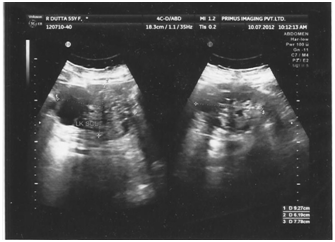

A 53years old obese woman presented with vague abdominal pain of one year duration. Physical examination was unremarkable. Ultra sonography of the whole abdomen detected an exophytic complex cystic lesion measuring about 10x8cm in upper pole of left kidney (Figure 1). MDCT whole abdomen showed 9.4x7.7x7.5cm sized multiloculated cystic lesion with enhancing septae and calcifications with solid nodular areas (Figure 2). The patient was diagnosed as Stage II left Renal Cell Carcinoma and subjected to Radical Nephrectomy. Adrenal was also removed as the tumor was in upper pole. On gross examination the tumour was multi nodular. Cut surface shows a spongy mass measuring 11x8.5x5cm, filled with yellowish serous fluid in the upper pole. On microscopic examination, the tumour was composed of variably sized tubules and fenestrated channels lined by bland cuboidal cells to epithelioid cells. No mitosis, cytological atypia, or nuclear pleomorphism was seen. Remaining kidney showed patchy chronic pyelonephritis with glomerulosclerosis and scarring. The adrenal showed normal histological appearance. Histopathology of the tumor was suggestive of Adenomatoid tumor of kidney (Figure 3). The tumor was positive for vimentin on immunohistochemistry.

Figure 2 Multiloculated cystic lesion with enhancing septae and calcifications with solid nodular areas.